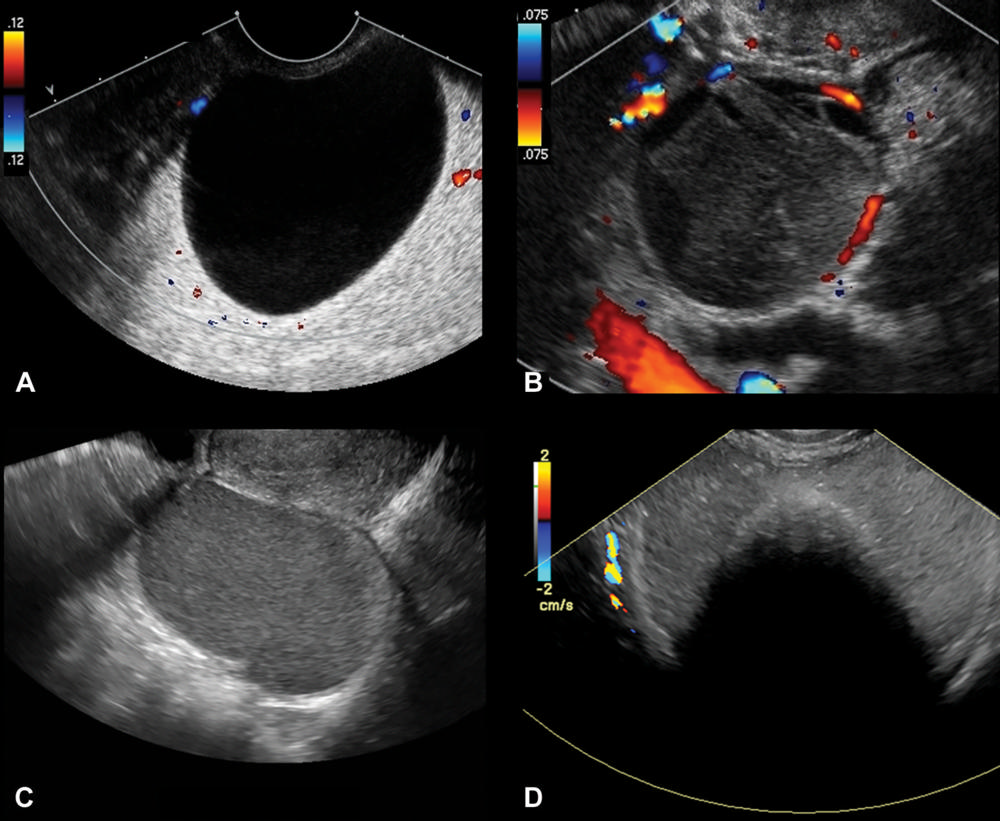

Figure 1. Representative transvaginal US images of classic lesions; color Doppler blood flow with color bar signifies direction of flow. (A) Transverse color Doppler image of right adnexa depicts an anechoic cyst with no internal elements or Doppler flow, compatible with a simple cyst. (B) Transverse color Doppler image of left adnexa depicts a cystic lesion with retractile clot and no Doppler flow, compatible with a hemorrhagic cyst. (C) Sagittal gray-scale image of left adnexa depicts a cystic lesion with homogeneous, low-level echoes or ground-glass appearance, compatible with an endometrioma. (D) Transverse color Doppler image of right adnexa depicts a lesion with echogenic components that demonstrate acoustic shadowing and no Doppler flow, compatible with ovarian dermoid.